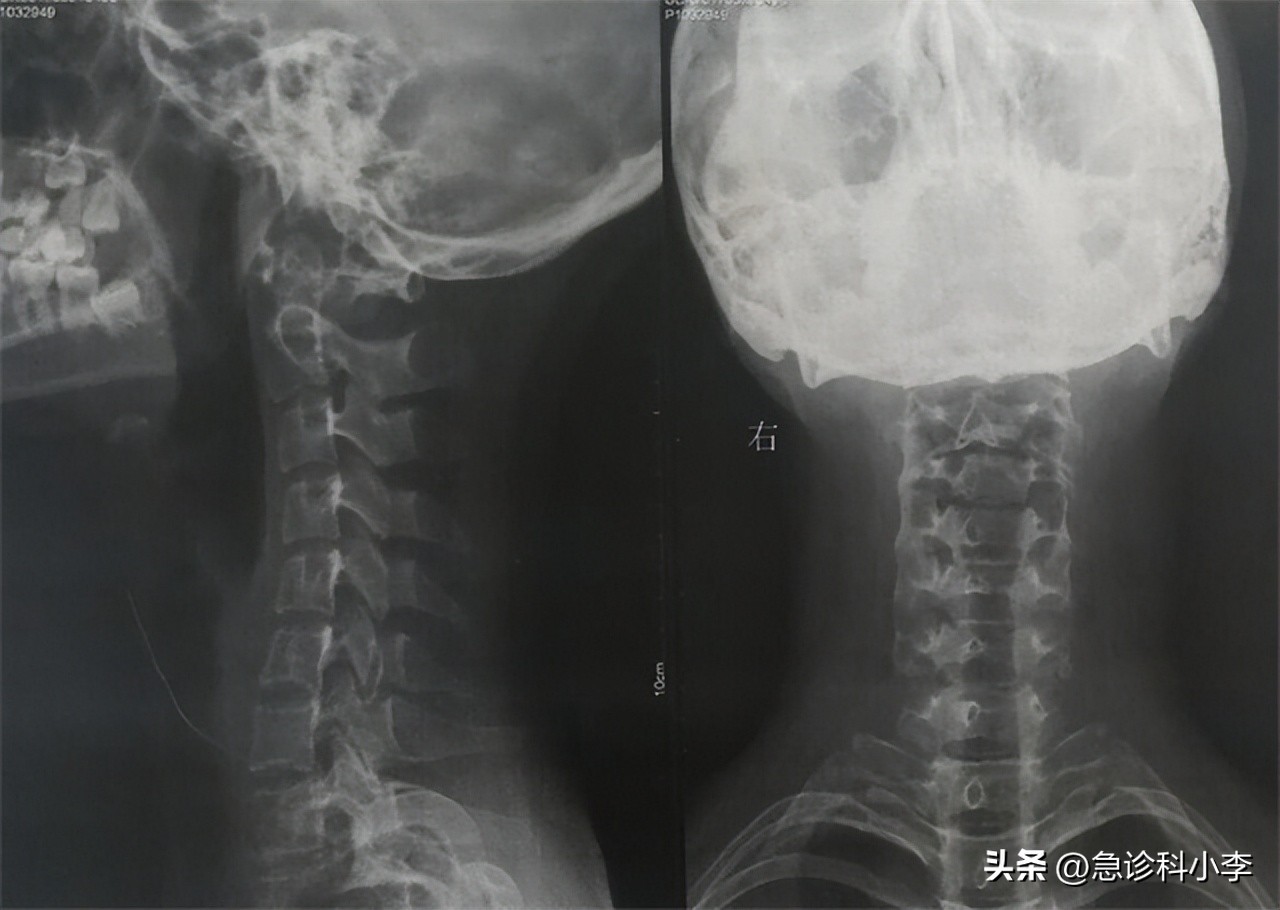

(4)颈部X线检查

一旦气管中出现浸润或者变形,则提示有恶性病变,X线也可出现 钙化表现 。所以,颈部X线还是可以用于甲状腺结节良恶性的判断的。